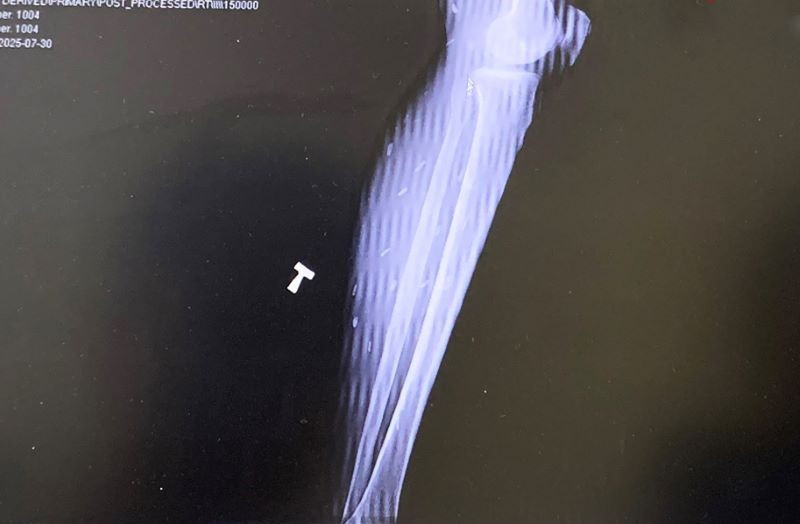

Hình ảnh chụp X-quang phát hiện sán dây ở chân 1 bệnh nhân - Ảnh BVCC

Mới đây bệnh nhân D.T.T (xã Ba Chẽ) nhập Bệnh viện Đa khoa tỉnh Quảng Ninh trong tình trạng đau đầu, đau mỏi cơ kéo dài. Theo bệnh nhân, các triệu chứng này xuất hiện từ nhiều năm trước. Kết quả xét nghiệm của Bệnh viện cho thấy bệnh nhân mắc sán dây, cần được điều trị nội trú theo phác đồ.